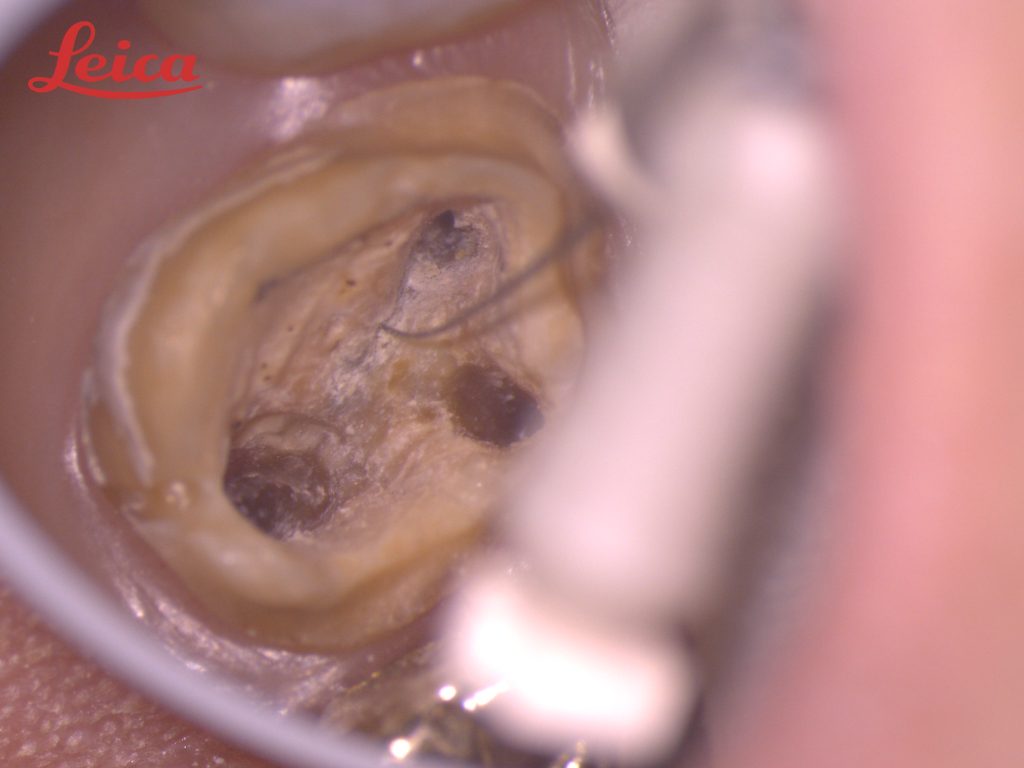

一度 根管治療したにも関わらず、再度膿が出てきたこちらの左上第一大臼歯。

すでに、3つの根の治療が施されておりましたが、マイクロスコープを用いて注意深く歯の溝をたどってみます。

4本目の根が出てきました。 この歯は高い確率で 4本目の根がある事が知られていますが、肉眼でこの根を発見するのは、ほぼ不可能です。